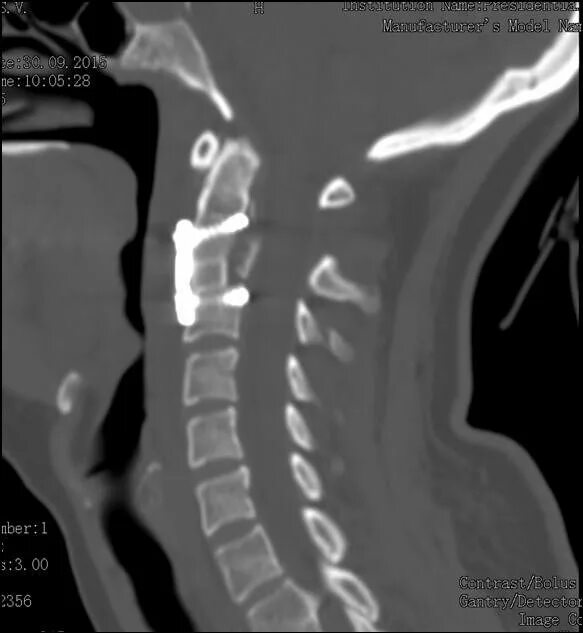

Перелом позвонка инвалидность